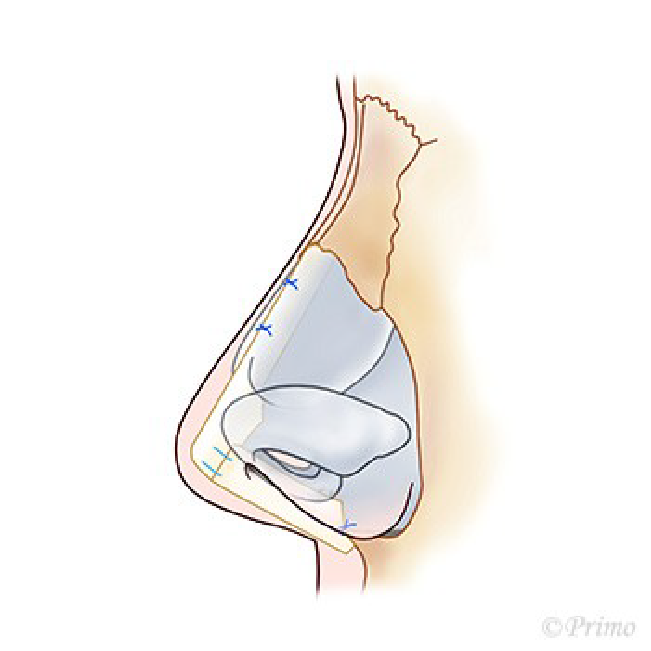

求める変化の大きさ、もともとの鼻の状態に応じ、採取部位を耳介軟骨、肋軟骨、あるいは鼻中隔軟骨から選択し、必要量のみ採取いたします。(上の図は耳介軟骨を採取して鼻中隔延長をするイメージ)

アプローチは経鼻柱切開(オープンアプローチ)から、術野を広く展開し、確実に操作を行います。鼻中隔軟骨に移植軟骨を組み合わせ延長し鼻の向き、高さを変えていきます。ご希望に応じ鼻の脂肪を部分的に除去し細っそりとさせたり、インプラントによる隆鼻術を併用し、より印象的な鼻に変化させます。鼻柱の傷あとはあまり目立ちません。

青い部分が移植した軟骨です。この軟骨の固定により、鼻の高さ、細さ、向きが大きく調節できます。